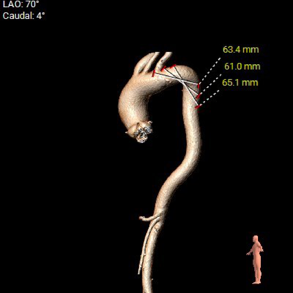

外周血管入路评估

5. 主动脉弓、右侧髂总动脉可见散在钙化斑块,双侧股动脉穿刺处未见明显迂曲、钙化、狭窄,入路血管内径尚可。

• 主动脉弓、右侧髂总动脉可见散在钙化斑块,入路规范操作,小心通过,避免入路相关并发症。

随着TAVR技术在国内的普及,主动脉瓣狭窄患者有了更多的治疗选择。本例病人为主动脉瓣重度狭窄伴轻度反流,手术指征明确,患者明确拒绝外科手术,术前解剖形态评估适宜行TAVR手术,有TAVR手术指征。经罗骏、崔凯教授团队的综合评估,结合心内科、心外科、超声等多学科团队的讨论意见,最终决定为患者施行TAVR手术治疗。手术过程中,TaurusElite经导管主动脉瓣输送系统在保持回收性能稳定的同时兼具优异的柔顺性,顺利完成过弓、跨瓣操作。其次,针对本例患者钙化较重、瓣叶局部粘连的特点,TaurusElite瓣膜高密度流入端设计提供了足够的径向支撑力,保证了瓣膜的锚定力;低密度流出端的设计也兼具柔顺性,能帮助术者更好的完成过弓与跨瓣操作。此外,TaurusElite瓣膜内外双裙边设计能有效减少瓣周漏,适度的收腰既能保证足够的有效瓣口面积,又降低了冠脉阻挡风险。最后,面对临床复杂的解剖结构特点,瓣膜释放过程中可能出现瓣膜下滑或上跳的风险,增加了术中释放瓣膜的难度;而TaurusElite瓣膜系统具有多次原位回收、回收后可重新跨瓣等设计特点,让术者释放过程中更有信心,能降低手术风险,减少并发症的产生,从而让患者得到更好的预后。本例患者术中的情况验证了术前CT分析的准确性,最终瓣膜释放位置良好,冠脉血流灌注正常,术后压差明显降低,术后跨瓣压差从101mmHg降至2mmHg,仅有微少量瓣周漏。术后病人恢复良好,各项生命体征平稳,手术效果十分优异。